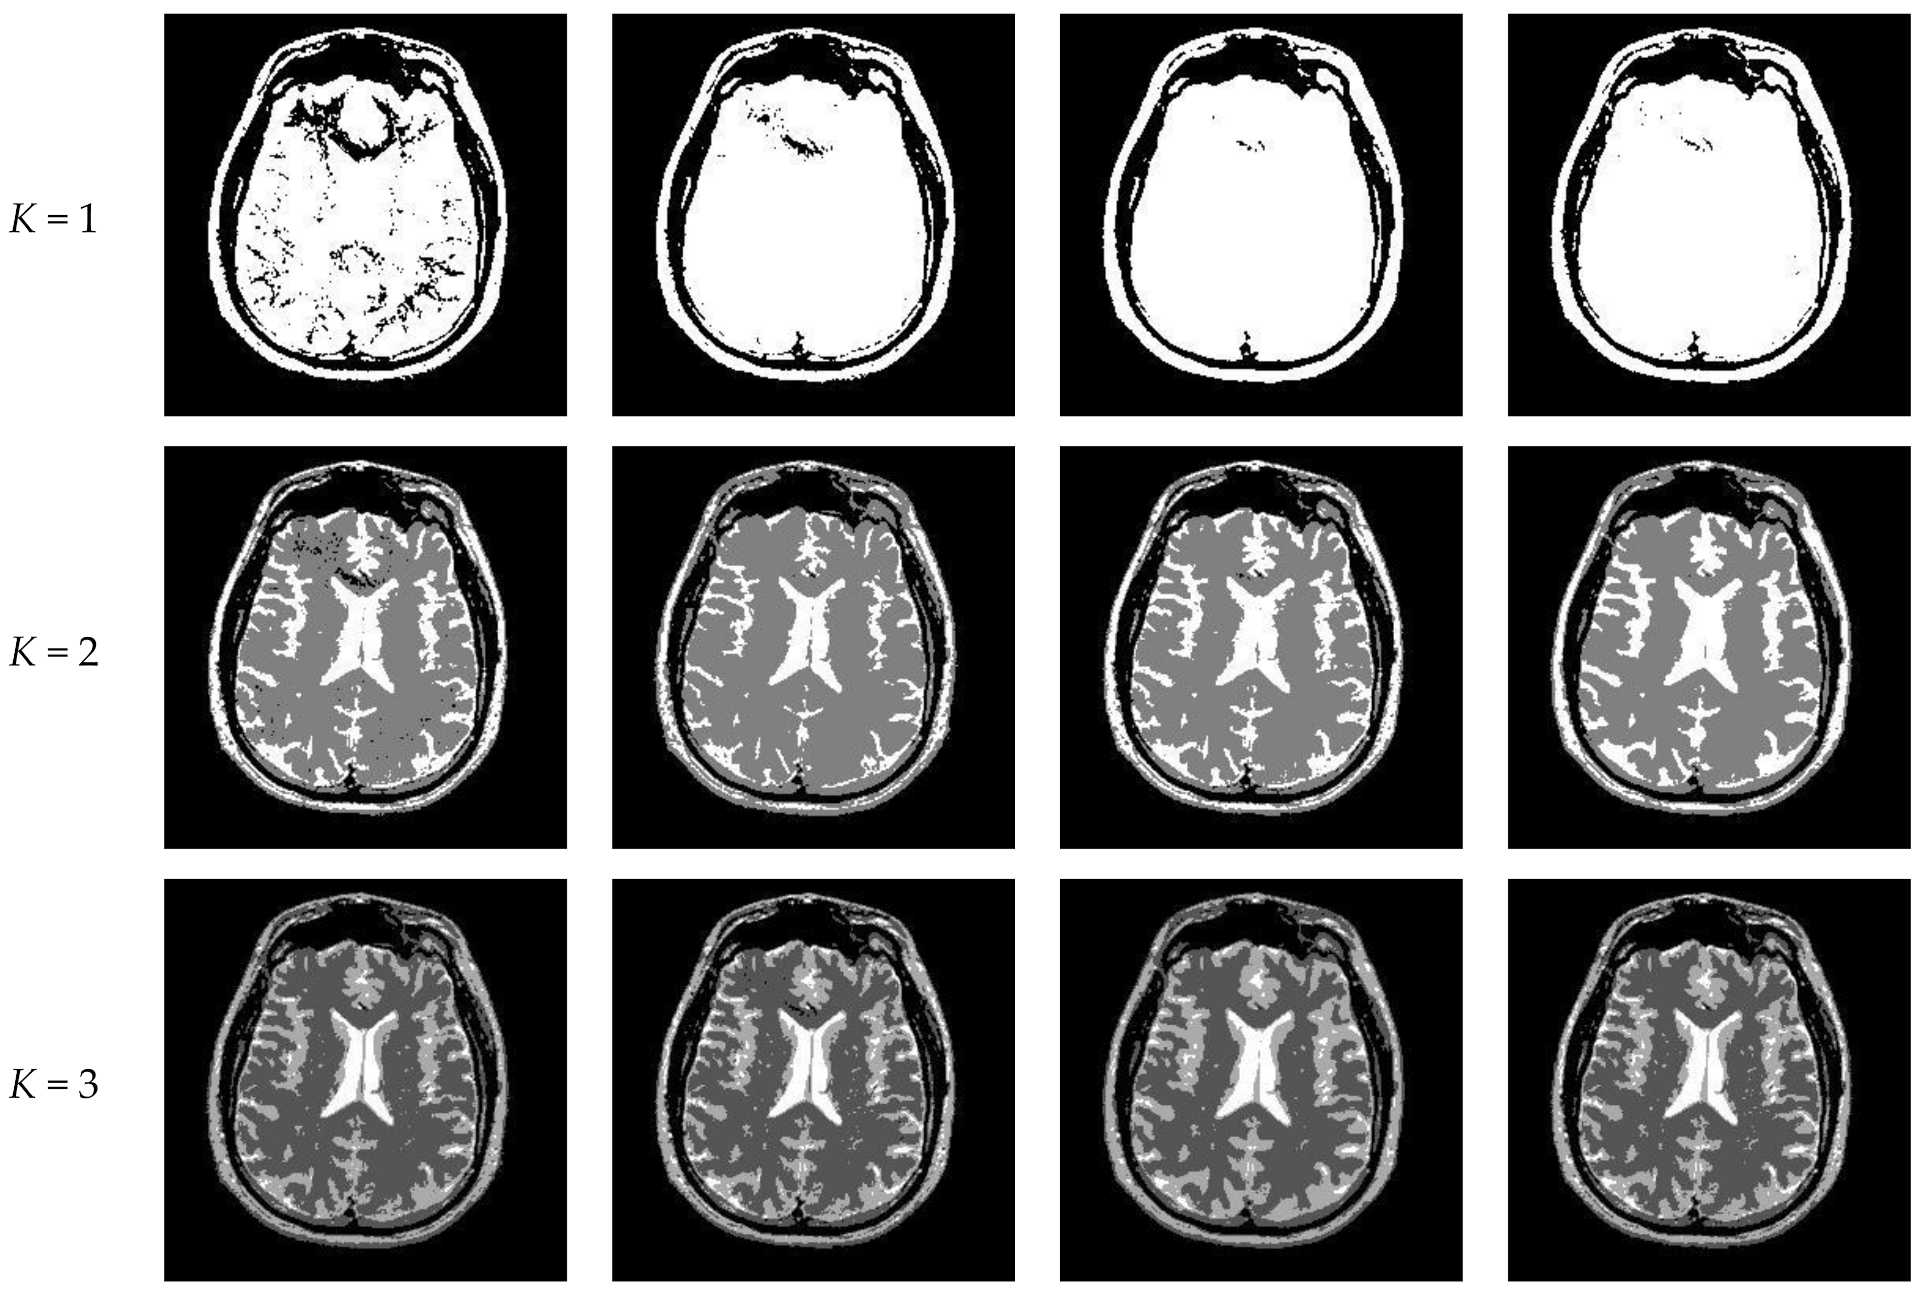

Figure 14 displays the segmentation results of images containing noise with a single level of thresholding K = 1. It can be observed that segmentation results achieved by HL-IIMT and Proposed are distinctly better than those of Otsu and IIMT, which have many isolated points. Figure 15 depicts segmentation results obtained by different algorithms with multilevel thresholding K = 4. Obviously, segmentation results of Otsu, IIMT, and HL-IIMT are seriously affected by noise, and most regions are blurred. However, the results of Proposed are better, and they have less noise and clearer edges.

Figure 14.

Segmentation results obtained by different segmentation algorithms for images containing noise (K = 1): (a) Otsu, (b) IIMT, (c) HL-IIMT, (d) Proposed.

Figure 15.

Segmentation results obtained by different segmentation algorithms for images containing noise (K = 4): (a) Otsu, (b) IIMT, (c) HL-IIMT, (d) Proposed.

A comparison of the evaluation results for different segmentation algorithms on images containing noise with K = 1, 4 is shown in Table 3, and corresponding comparison charts are given in Figure 16. In Table 3, the best results are marked in bold. It can be noted that Proposed consistently has the highest U values. For images containing noise, both the IIMT-based algorithms (HL-IIMT and Proposed) are superior to the original Otsu method in single threshold segmentation; furthermore, Proposed can achieve satisfactory results in multilevel threshold segmentation compared to the other three algorithms (IIMT, HL-IIMT, and Otsu).